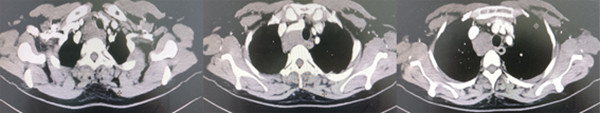

患者曹某某,女,48岁,2年前行胸部CT检查示:右侧颈根部、前上纵隔占位,于当地医院行“右侧颈部纵隔肿瘤探查术”,但因肿瘤“血供丰富,包饶重要脏器”无法切除肿瘤。患者术后出现声音嘶哑,且有颈部肿胀和胸背部等不适症状。后患者在当地医院行介入治疗,但仍无改变,且上述症状加重,出现气管压迫,气短憋气,遂于2021年6月25日来我院胸外科就诊。入院后行胸部CT检查示:胸廓入口处、上纵隔气管右旁可见不规则软组织密度影,病变密度不均,边界欠清晰,大小约6.2cmX3.7cmX3.3cm。鉴于患者症状逐渐加重,病变范围大,位置特殊,经全科讨论并与患者及家属沟通后,决定手术方案为“纵隔肿瘤切除术”。经过充分的术前准备,于2021年7月6日在麻醉科团队先进行全身麻醉后,胸外科李少民主任团队进行手术操作,因二次手术,解剖结构消失,粘连一团,术中仔细游离并显露做无名静脉、头臂干动脉、右颈总动脉、右锁骨下动脉,右颈内静脉、气管及食管等结构,充分暴露术野,完整切除了纵隔肿瘤,以及侵及周围组织,手术过程顺利,历时3小时,术后患者生命体征平稳,拔除气管插管后安全返回胸外科监护室,目前患者病情稳定。